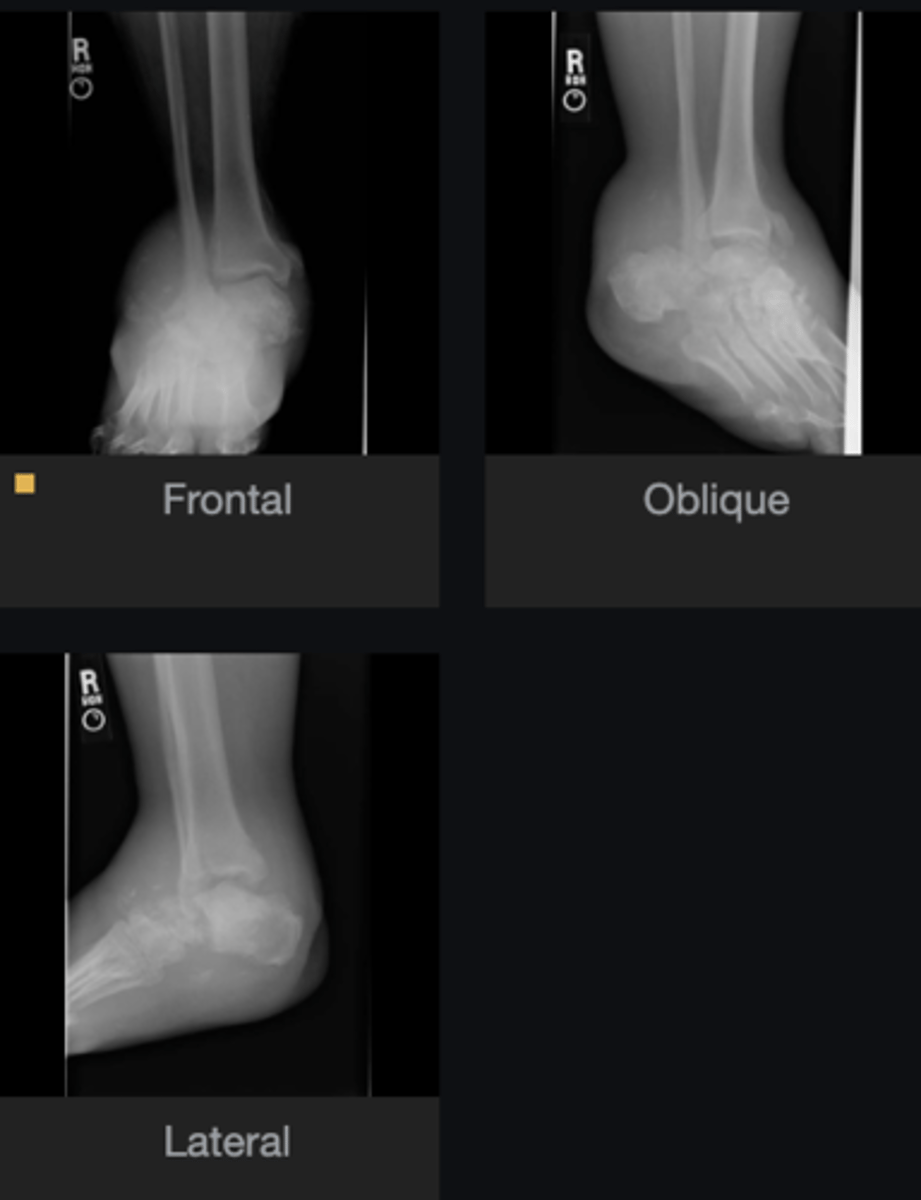

- Swelling (distension)

- Dislocation

- Destruction

- Density changes

- Debris

- Disorganization

Describe findings

- Neuropathic arthritis

- Diabetes, neurosyphilis, syringomyelia, myelomeningocele, alcoholism

- Diagnosis?

- What are some causes of this?

Primary care provider

Next step?

No

Would you adjust the ankle?

- Intra-articular calcifications

- Loose bodies

List main findings

- Osteophytes

- Unilateral loss of joint space

Any secondary findings?

Synoviochondrometaplasia (SCM)

Diagnosis?

Orthopedic surgeon referral